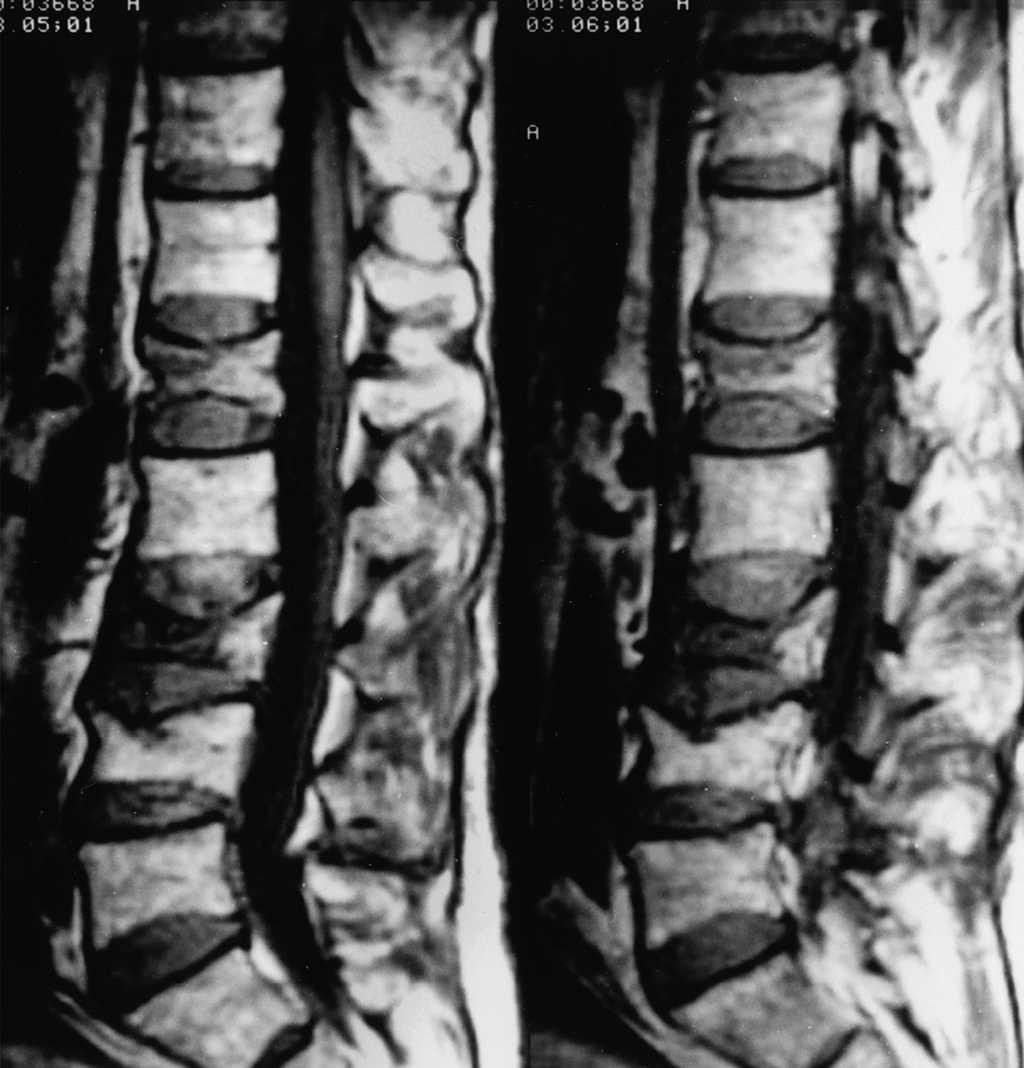

Fractura aplastamiento vertebral por fragilidad

10 agosto 2020

La fractura vertebral por compresión (aplastamiento vertebral) es considerada la fractura osteoporótica más común. Puede causar dolor agudo y/o crónico, aunque a menudo pasa desapercibida y no es diagnosticada. Constituye un factor de riesgo independiente de nuevas fracturas vertebrales y de otras localizaciones, y se asocia a un exceso de mortalidad. En la mayoría de los pacientes, el dolor remite en unas semanas, aunque en un porcentaje de ellos el dolor puede persistir durante más tiempo con discapacidad o incluso requerir ingreso hospitalario para controlar el dolor. FMC, agosto de 2020